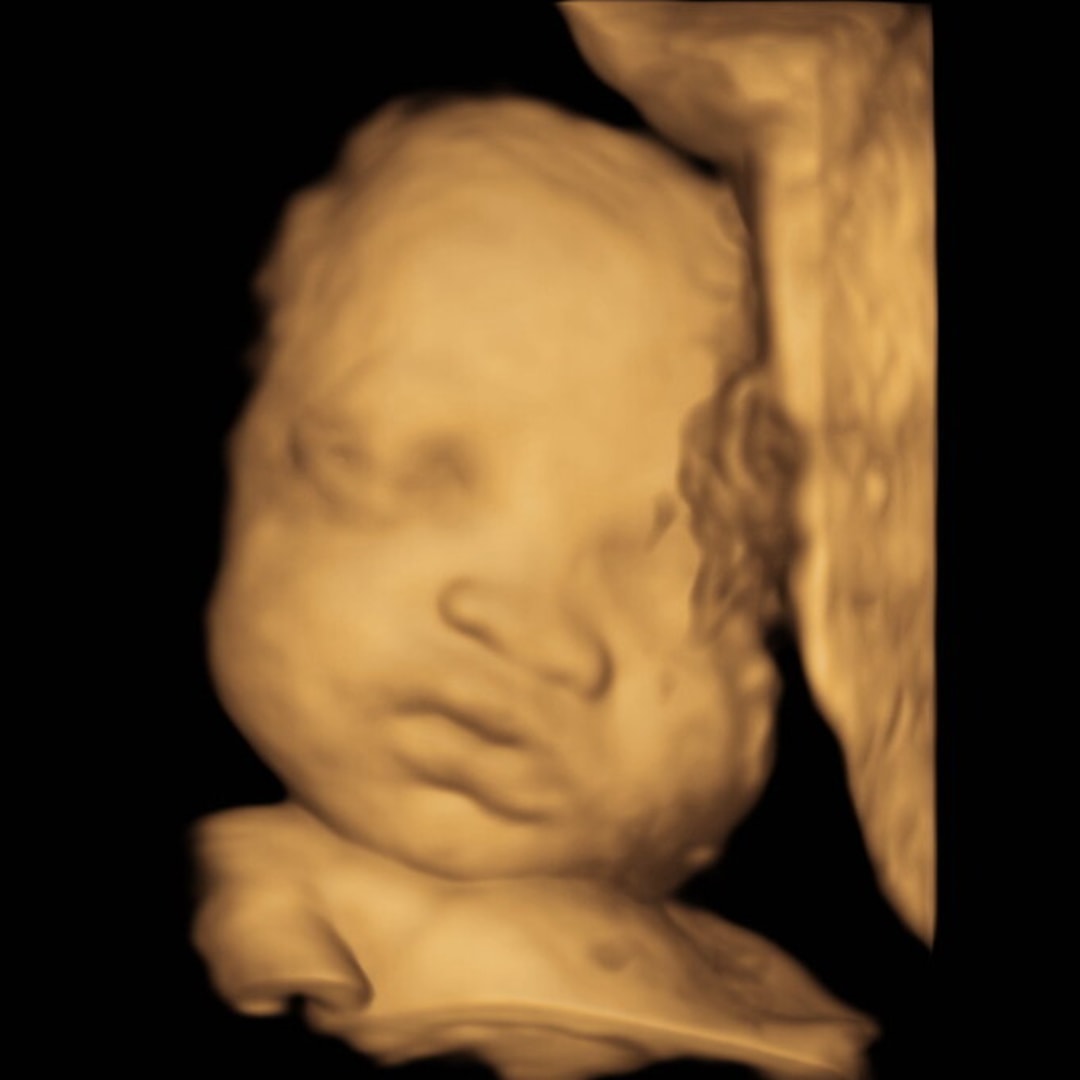

Baby girl!